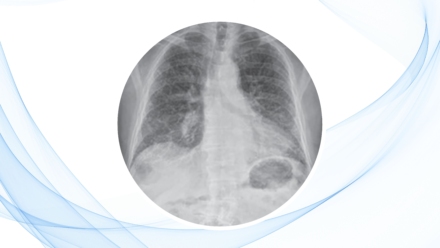

Cuidados Intensivos Neumología Fibrosis pulmonar idiopática: diagnóstico y manejo by Amolca 19 diciembre, 2025 836Views 0Comments Este artículo se basa en el contenido del libro Enfermedades pulmonares poco frecuentes e intersticiales, una obra de Claudio Sorino y Sergio Agati.